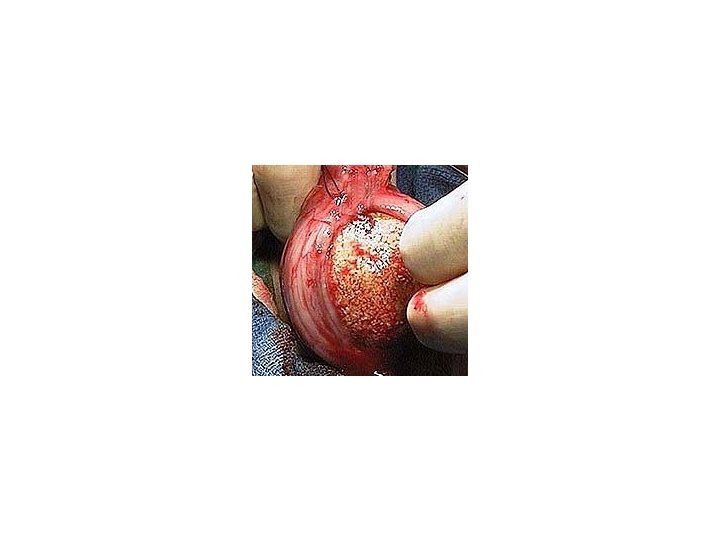

Calcium oxalate stones can not be dissolved by diet and must be surgically removed. 50% of animals who undergo cystotomy sx will redevelop stones within 3 years.

Cystotomy :